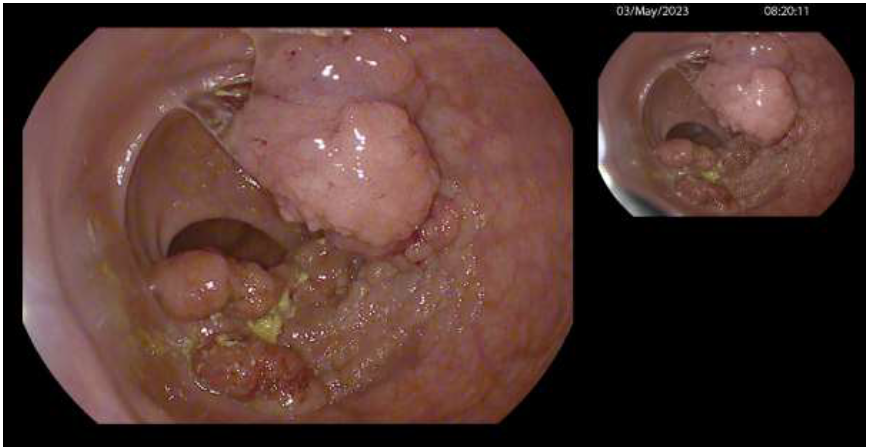

Here we report the case of a 77-year-old ASA 2 woman, who underwent to colonoscopy for sideropenic anemia and positive FIT. Examination showed a rectal granular nodular-mixed laterally spreading tumor (GM-LST) with a dominant nodule of 5 cm and a psudodepressed central area [figure 1,2]. The lesion was extended on the two third of rectal circumference involving the second and the third Huston fold and was judged suspected for invasive carcinoma. The histological examination reported low and high-grade dys-plasia. At total body computed tomography (CT)  no metastatic lesion was detected. Pelvic magnetic reso-nance (MRI) was consistent with T2N0, showing the extension of the lesion nearby the muscularis propria, without a clear distinction plane. In addition, a rectal endoscopic ultrasound (EUS) was requested, confirm-ing the MRI findings. Given the well-known risk of EUS and MRI overstating, as reported by recently re-leased ESGE guidelines [4] and after a gastrointestinal multidisciplinary team (MDT) discussion, the pa-tient was proposed for endoscopic submucosal dissection4. For the procedure, we used a standard   diag-nostic Pentax gastroscope  mounted with a conic distal end cap (ST Hoods, Fujifilm®). First, a mucosal incision was made approximately 5mm around either the proximal and distal side of the rectal lesion, fol-lowed by submucosal dissection using DualKnife J 1.5mm (Olympus®). During the dissection, a deeper submucosal invasion was suspected  beneath  the dominant sessile nodule, where the submucosal space was progressively disappearing for muscular retraction and also for fibrotic reaction [Figure 3]. In this area we moved to the inner circular muscular layer dissection, even using the same small tip knife. The dissec-tion was completed using the Hook Knife J (Olympus) for the lateral part, resulting in complete resection of the lesion, 10x6 cm in size [Figure 4]. The resection phase took 90 min. Hemostasis  was achieved with monopolar  forceps (Coagrasper - Olympus®). The base was sutured using through-the-scope clips and a hemostatic matrix (Purastat®, 3ml) was apposed  to prevent delayed bleeding. Precautionary, the patient was hospitalized for three days and then discharged after uneventful observation. Histological examination of the lesion reported well-differentiated adenocarcinoma (G1) focus over a high-grade dysplasia tubulovil-lous adenoma, no tumoral budding or vascular invasion, absence of tumor on the resection plane and sub-mucosal invasion limited to 500 μm. Histopatology also showed the circular muscular layer on the resection plane of the lesion  [Figure 5]. MDT indication was endoscopic follow-up after 6 months.

Figure 2